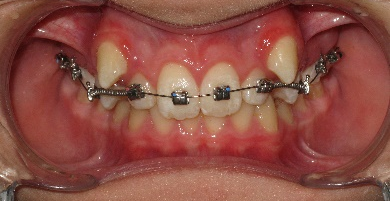

В последующем, после дистализации моляров на верхней челюсти, аппарат снят и на втором этапе ортодонтического лечения фиксирована брекет-система пассивного самолигирования NexStep Pro с пазом 0.22 (стандарт). Уникальная конструкция замка-слайда обеспечивает повышенный контроль торка и ротации, а прецизионность паза брекета дает полную реализацию программы, заложенную в брекетах данной системы SLS. (рис.6 )

После дистализации боковых сегментов на верхней челюсти и правильной постановки клыков в зубной ряд проведена фиксация аппарата на нижний зубной ряд и дальнейшая коррекция окклюзии проводится по стандартному протоколу, т.е. нормализация формы зубных рядов на верхней и нижней челюсти с правильной постановкой зубов по торку в боковых и во фронтальном отделах, что дает реализация программы, заложенная в пассивной самолигирующей брекет- системе NexStep Pro 0.22. (рис.8)

Рис.8. Этап контроля торка на верхней челюсти и фиксация аппарата на нижней челюсти для проведения этапа нивелирования.